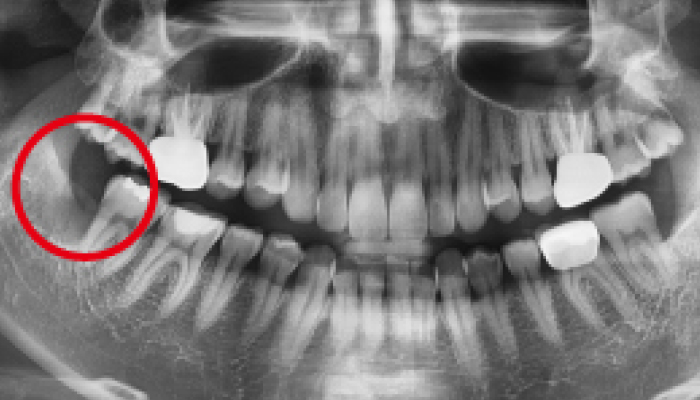

이갈이는 다양한 원인에 의해 발생되는 것으로 치아의 마모, 턱관절 통증, 두통 등을 유발합니다. 치과치료와 함께 생활습관을 교정하는 방법으로 이갈이를 줄여나갈 수 있습니다.

이갈이 원인

• 01 '이악물기' 습관

이 악물기 습관은 근육의 긴장도를 증가시키고 치아에 무리한 힘을 가해, 이갈이 증상을 유발하기기도 합니다.

다양한 합병증을 동반하는 이갈이